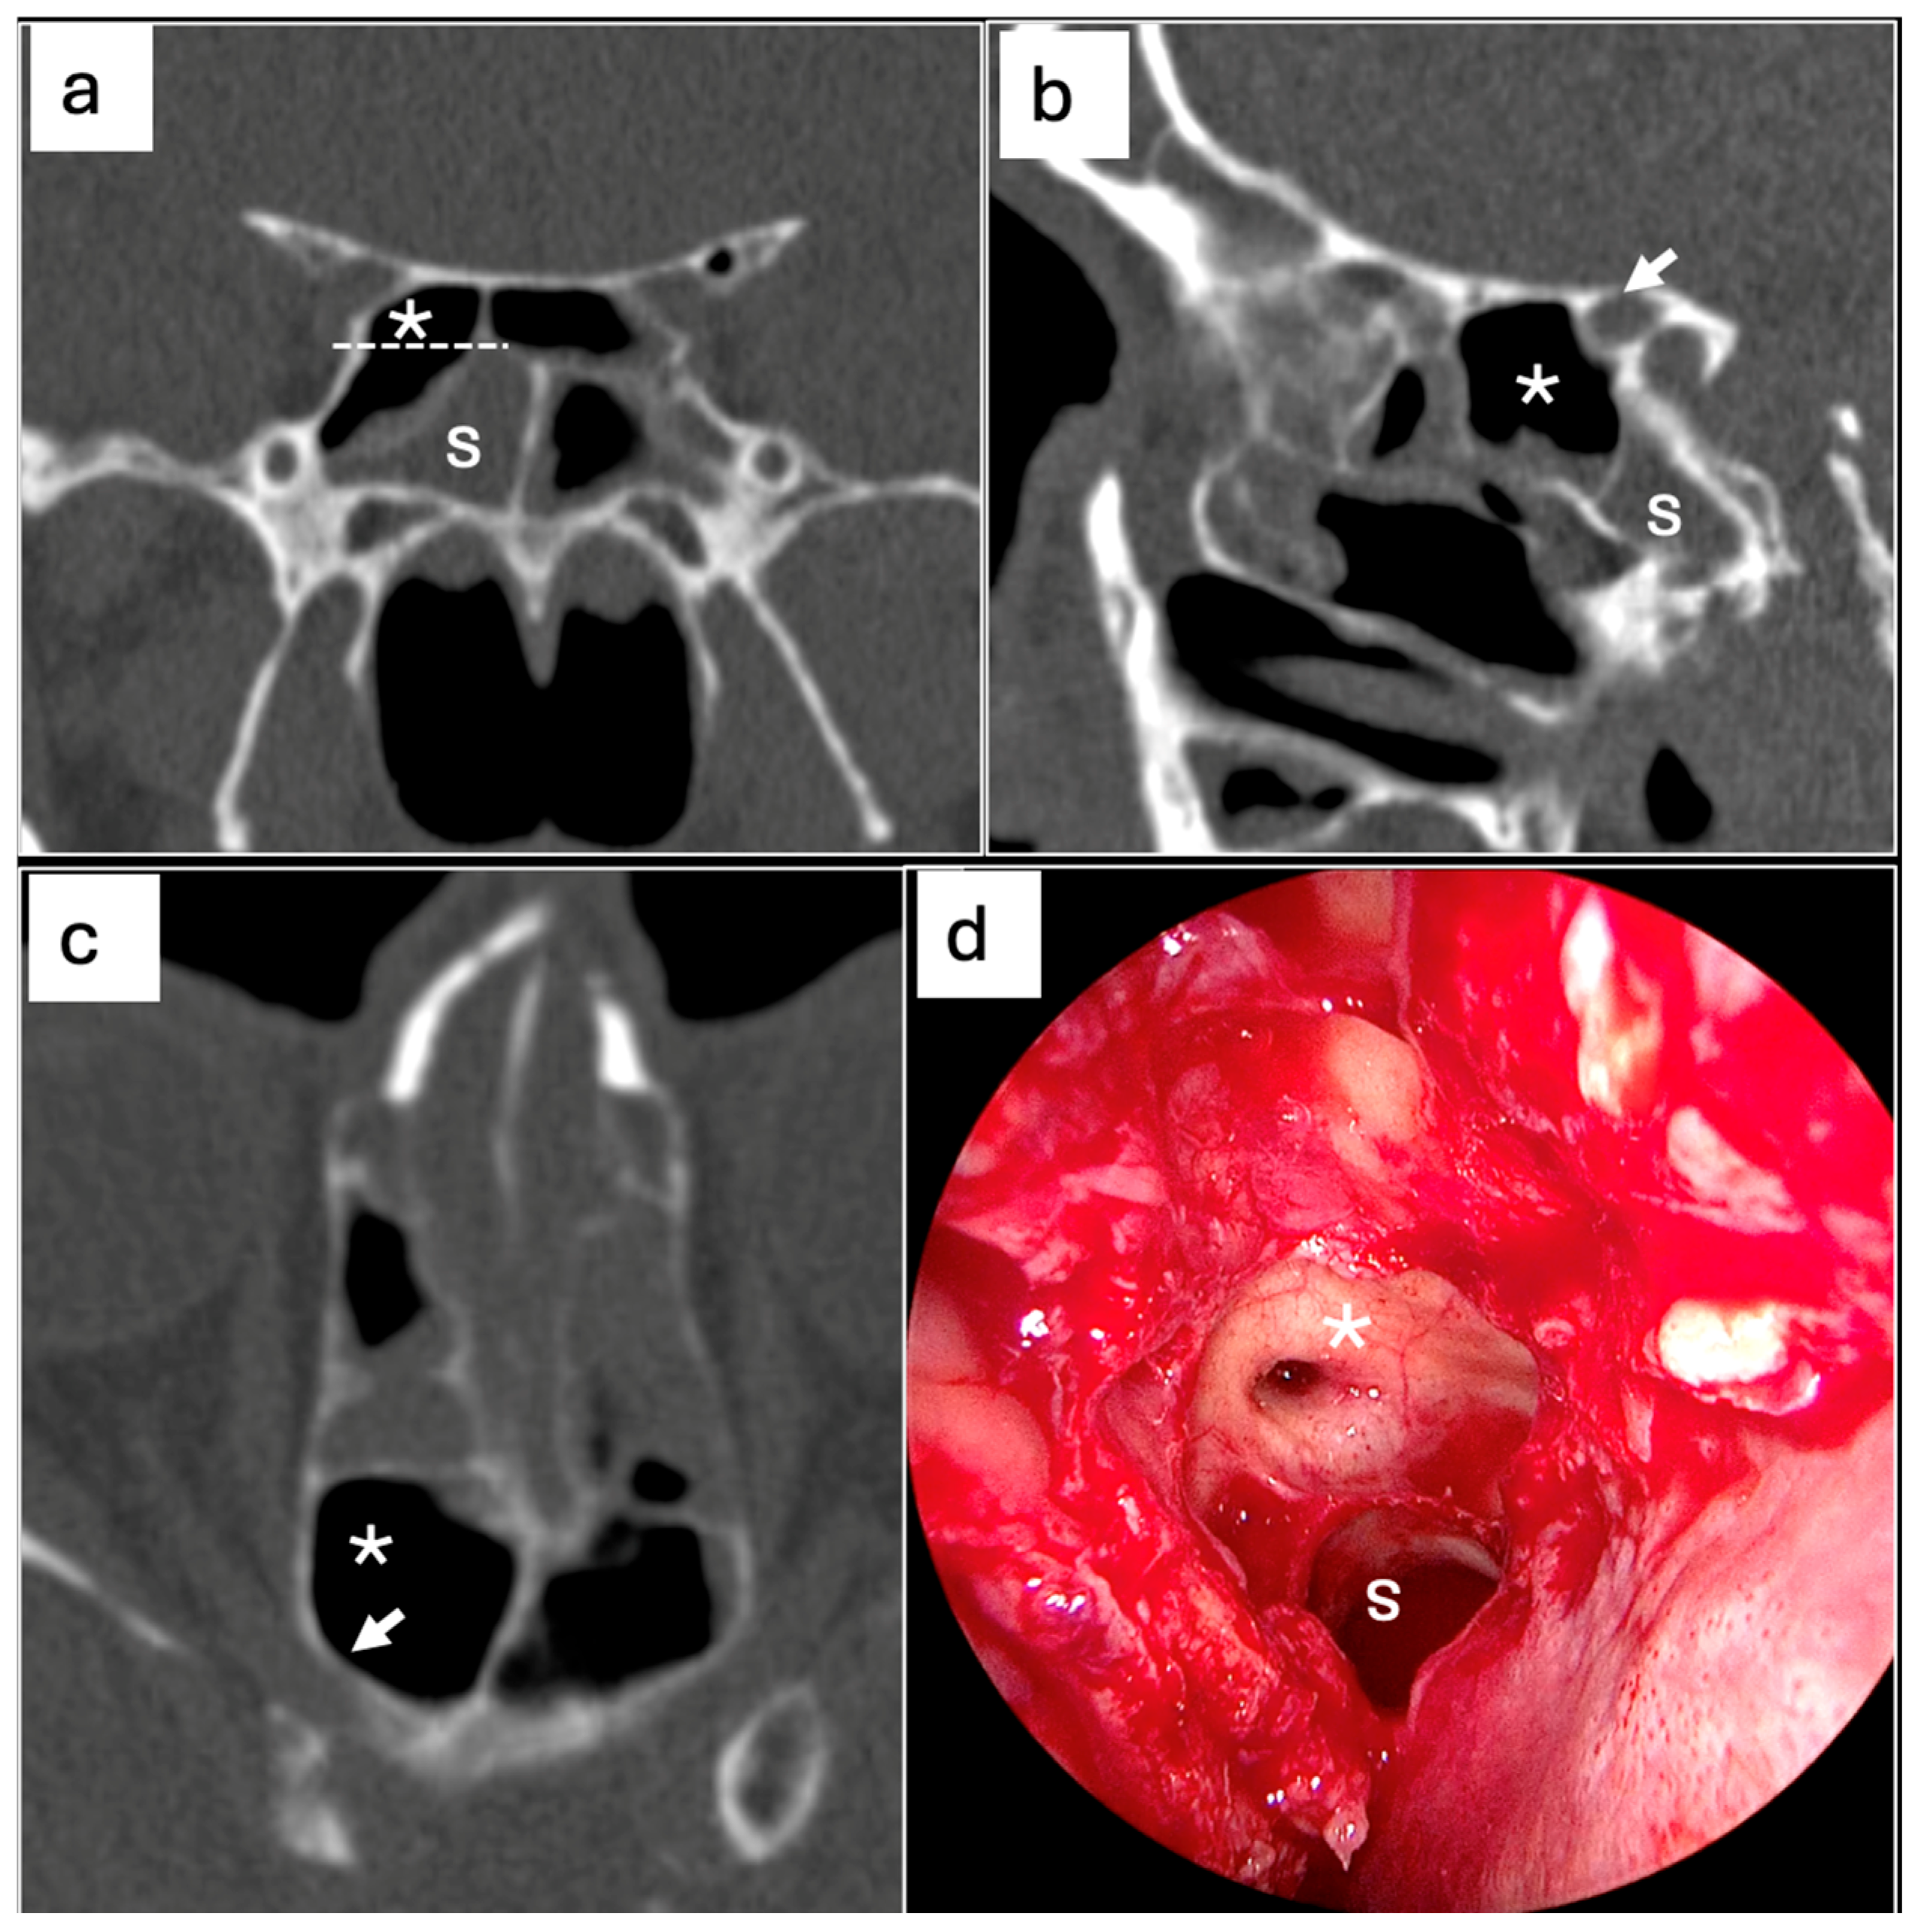

- Fadda, G.L.; Urbanelli, A.; Petrelli, A.; Trossarello, M.; Nitro, L.; Saibene, A.M.; De Corso, E.; Gned, D.; Panfili, M.; Cavallo, G. Type IV optic nerve and Onodi cell: Is there a risk of injury during sphenoid sinus surgery? Acta Otorhinolaryngol. Ital. 2024, 44, 36–41. [Google Scholar] [CrossRef] [PubMed] [PubMed Central]